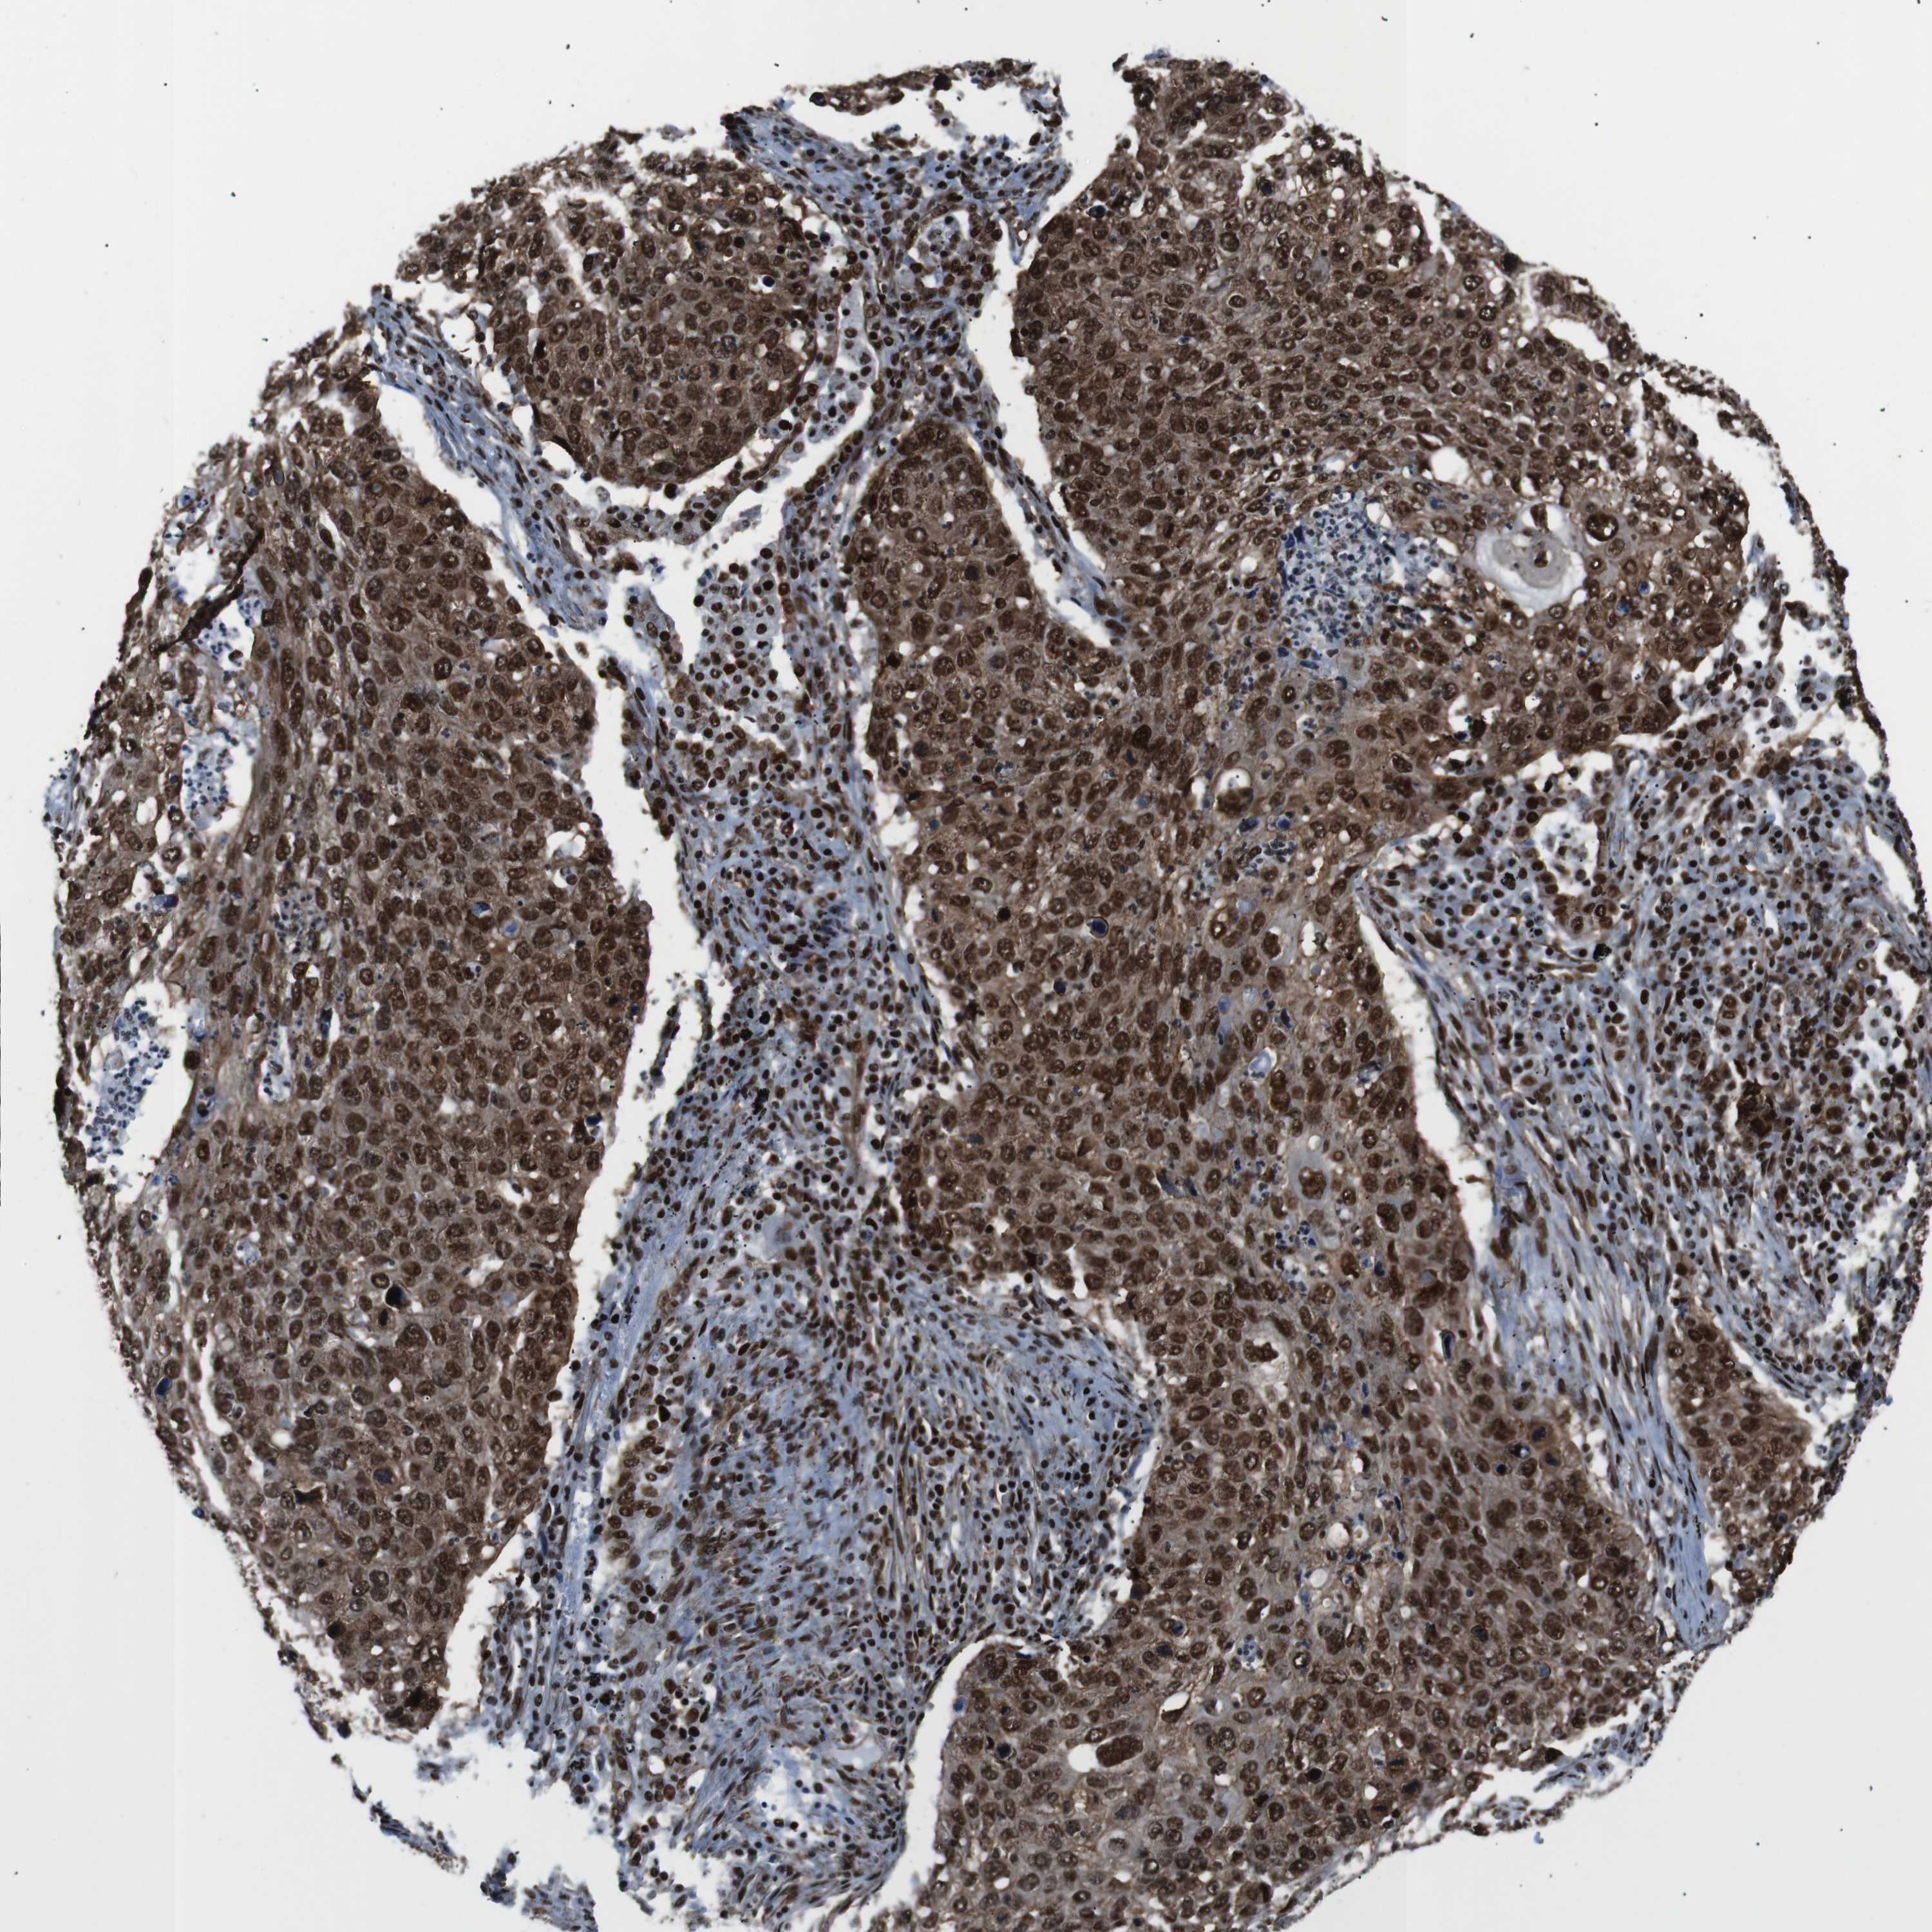

LUNG SQUAMOUS CELL CARCINOMA (TCGA) - Interactive survival scatter ploti

The Survival Scatter plot shows the clinical status (i.e. dead or alive) for all individuals in the patient cohort, based on the same data that underlies the corresponding Kaplan-Meier plots. Patients that are alive at last time for follow-up are shown in blue and patients who have died during the study are shown in red.

The x-axis shows the expression levels (FPKM) of the investigated gene in the tumor tissue at the time of diagnosis. The y-axis shows the follow-up time after diagnosis (years). Both axes are complimented with kernel density curves demonstrating the data density over the axes. The top density plot shows the expression levels (FPKM) distribution among dead (red) and alive patients (blue). The right density plot shows the data density of the survived years of dead patients with high and low expression levels respectively, stratified using the cutoff indicated by the vertical dashed line through the Survival Scatter plot. This cutoff is automatically defined based on the FPKM cutoff that minimizes the p-score. The cutoff can be changed by dragging the vertical line or by entering a cutoff value in the square labeled "Current cut-off".

Under the Survival Scatter plot the p-score landscape (black curve; left axis) is shown together with dead median separation (red curve; right axis). Dead median separation is the difference in median mRNA expression between patients who have died with high and low expression, respectively. It is calculated as follows: median FPKM expression of dead patients with high expression - median FPKM expression of dead patients with low expression. This is intended to aid the user in visually exploring custom cutoffs and the associated p-scores and dead median separation.

Individual patient data is displayed and can be filtered by clicking on one or more of the category buttons on the top of the page. Categories describing expression level and patient information include: high, low, alive, dead, female, male and tumor stages. The scale of the x-axis can be toggled between linear and log-scale by clicking on the "x log" button. Mouse-over function shows TCGA ID, patient information and mRNA expression (FPKM) for each patient.

& Survival analysisi

Kaplan-Meier plots summarize results from analysis of correlation between mRNA expression level and patient survival. Patients were divided based on level of expression into one of the two groups "low" (under cut off) or "high" (over cut off). X-axis shows time for survival (years) and y-axis shows the probability of survival, where 1.0 corresponds to 100 percent.

HNRNPU is not prognostic in Lung Squamous Cell Carcinoma (TCGA)

Best expression cut offi

Based on the FPKM value of each gene, patients were classified into two groups and association between prognosis (survival) and gene expression (FPKM) was examined. The best expression cut-off refers the FPKM value that yields maximal difference with regard to survival between the two groups at the lowest log-rank P-value. Best expression cut-off was selected based on survival analysis .

When clicking on this number, the vertical dashed line indicating cut-off, the interactive survival plot, and the Kaplan-Meier curve will be adjusted to show results based on the best expression cut-off.

: 136.2

Median expressioni

P scorei

Log-rank P value for Kaplan-Meier plot showing results from analysis of correlation between mRNA expression level and patient survival.

N/A

TCGA RNA samplesi

RNA-seq data is reported as average FPKM (number Fragments Per Kilobase of exon per Million reads), generated by the The Cancer Genome Atlas (TCGA) .

Normal distribution across the dataset is visualized with box plots, shown as median and 25th and 75th percentiles. Points are displayed as outliers if they are above or below 1.5 times the interquartile range. FPKM values of the individual samples are presented next to the box plot.

Average pTPM 163.2

Number of samples 489